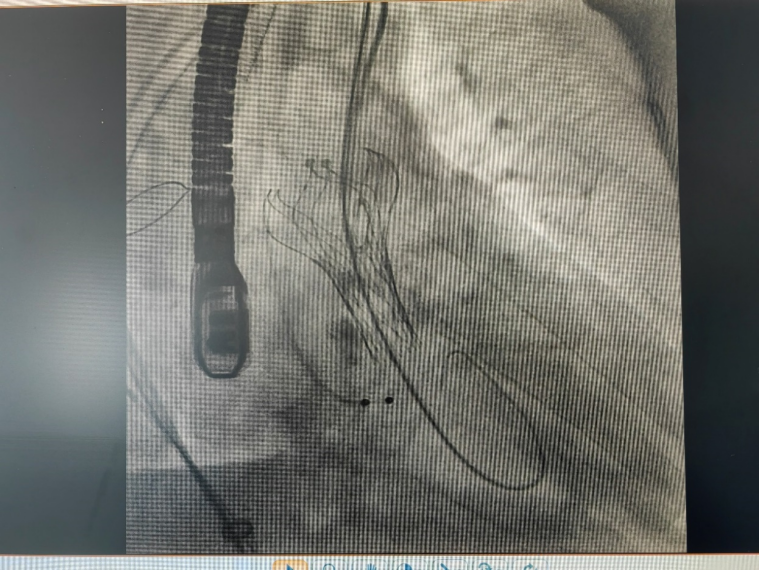

手术当日上午,由心脏中心主任杨成明教授主刀,心血管内科车小红、肖红霞、李子宁医生;心脏大血管外科乔军选主任;超声科邓旦主任;麻醉科董蜀华主任;介入护士李瑞全程参与手术,顺利经右侧股动脉途径成功为患者植入一枚 VitaFlow TAV21 人工主动脉瓣,术中造影及超声确认人工瓣膜位置良好,无明显主动脉瓣返流,术后主动脉瓣瓣压差显著下降至 10 mmHg、峰值血流速度降 2.1m/s,未见瓣周漏、心包积液,整台手术从穿刺血管到完成瓣膜植入,仅用时 1 小时 30 分。